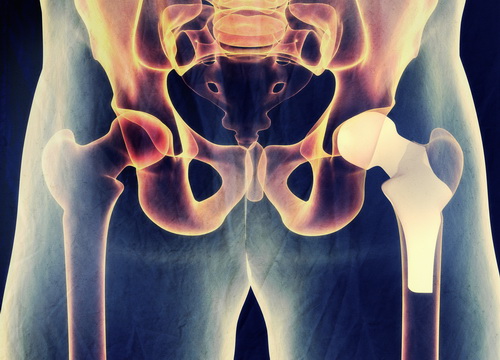

Зарубежные клиники по замене тазобедренного сустава, в том числе израильские, применяют эндопротезы ведущих мировых производителей, изготавливаемые из металла, пластика или керамики. Конкретный тип и способ его фиксации подбирается для каждого пациента индивидуально, с учетом возраста, уровня физической активности и других параметров. Для обеспечения идеальной «посадки» протеза используются технологии компьютерного моделирования. Преимущество такого подхода не только в том, что индивидуально разработанные импланты соответствуют всем анатомическим особенностям организма пациента, но и в том, что время на их установку значительно сокращается.

- Установка эндопротеза. В верхней части бедренной кости устанавливается металлический стержень, к которому крепится головка, после этого фиксируются вкладыш и чашка протеза.